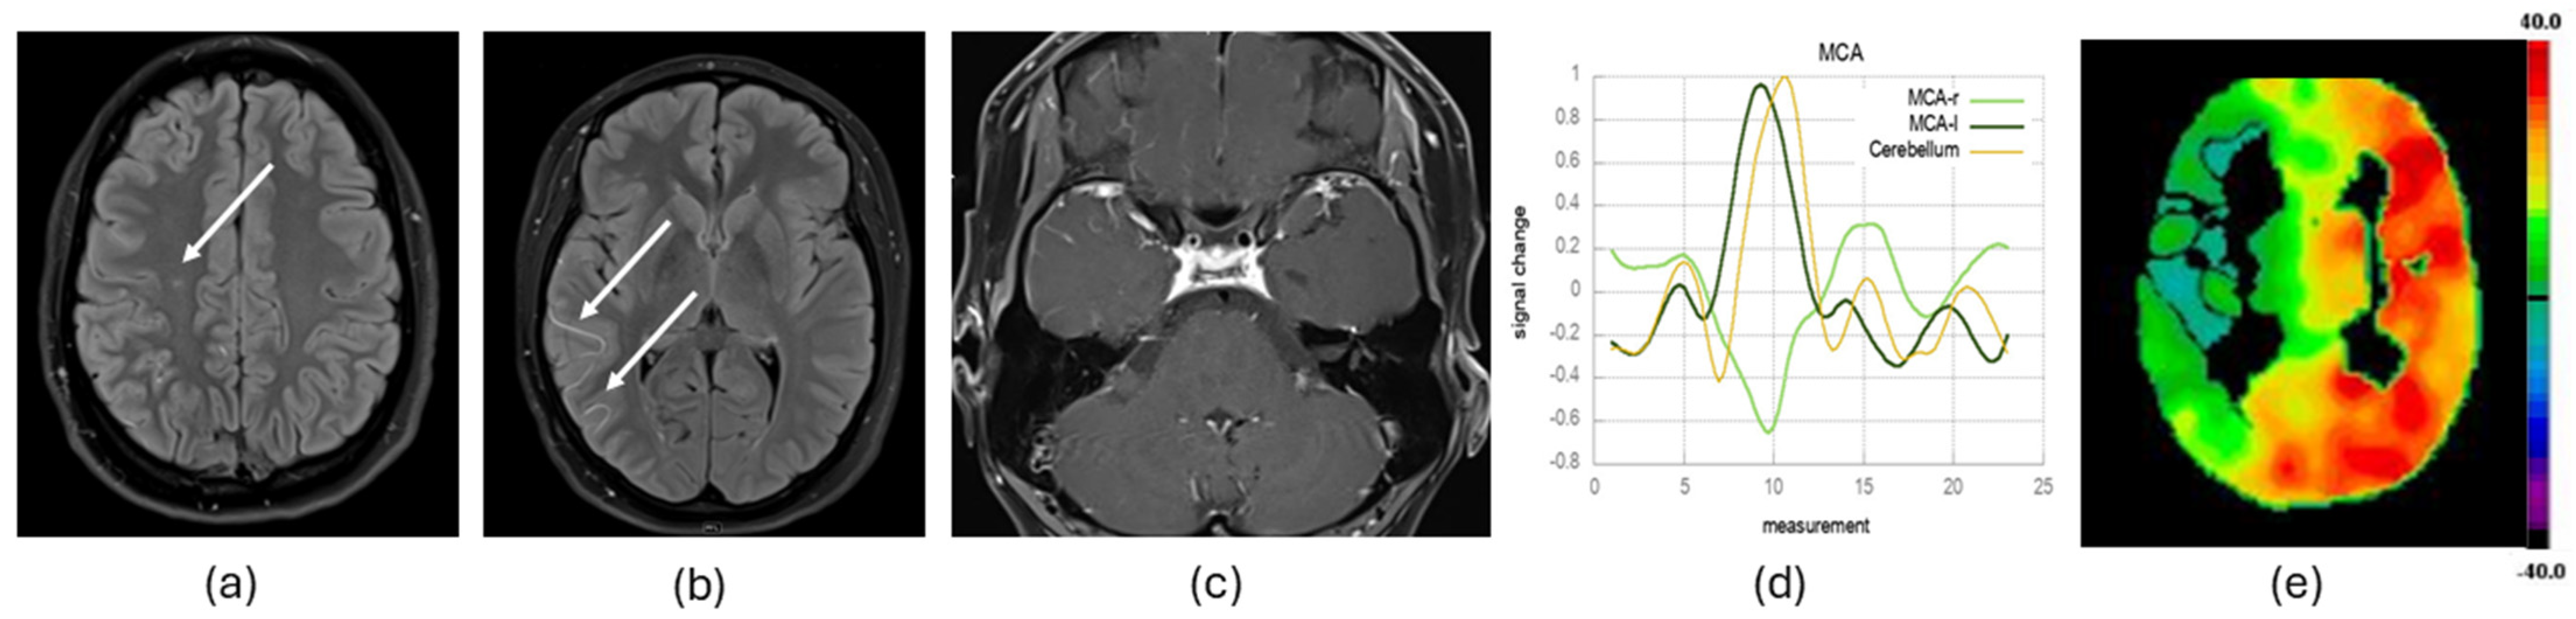

2.3.1. Structural MRI Data Evaluation

2.3.2. Functional MRI Data Acquisition, Processing and Evaluation

2.3.3. Arterial Wall Contrast Enhancement Evaluation

2.3.4. Ivy Sign Evaluation